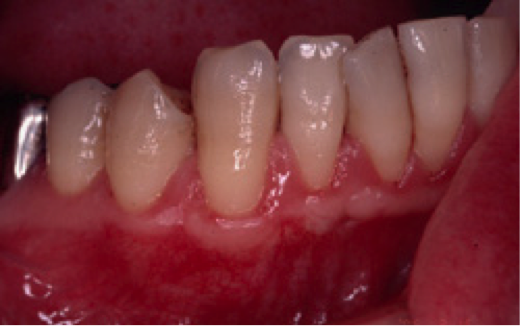

歯肉が全体的に下がっていることを主訴に来院されました。特にひどいのが右下の犬歯付近で、ここについては手術を受けてでも治したいとのことでした。このような状態を歯肉退縮と呼びますが、原因は大きく分けて二つ考えられます。一つは強く歯を磨きすぎること、もう一つは歯ぎしりなどの噛み合わせの不具合です。必ず事前の診査により原因を除去しておかないと、手術をして元通りになったとしても、またすぐに下がってしまいます。この症例では口蓋より結合組織を採取し、右下犬歯の部分に移植しました。

下は術後の状態です。術中の写真は痛々しいので割愛させていただきました。